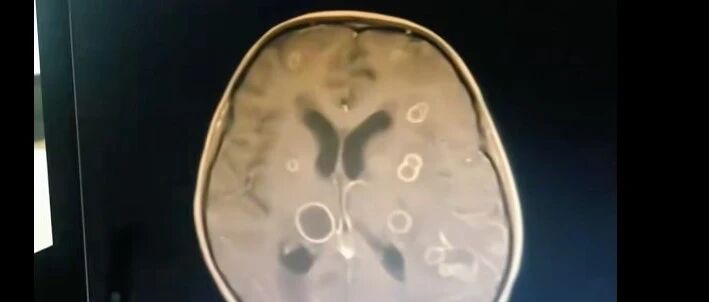

6岁女孩吸入霉菌,脑子被“啃”出十几个洞!家里这种情况要注意! 光明网 · 公众号 · · 3 小时前 · |